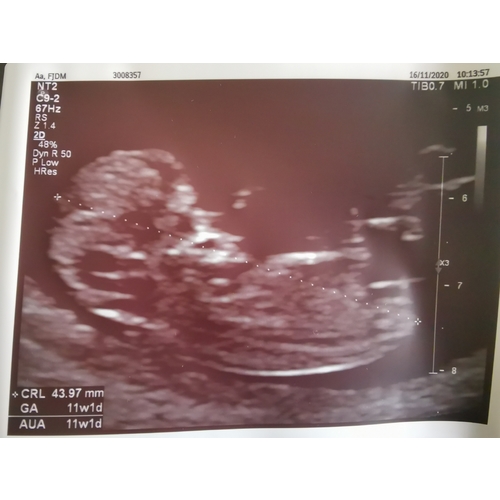

Vanmiddag de termijnen echo gehad, 19 oktober was ik 6 dagen terug gezet, vanmiddag bij de echo weer 6 dagen voorruit, de kleine deed het super, groeit goed en was een spring in het veld in de buik, heb een prachtig filmpje maar kan die niet plaatsen! Echt even een bevestiging van zwanger zijn! Ik heb 0.0 kwaaltjes dus maakte me toch wat zorgen dat het niet goed ging! Vandaag 11+4 wkn met de uitgerekende datum op 3 Juni 鉂も潳

Ahh, mooie echo!!! Ik had ook vandaag nu 11+1馃挄

Vandaag ook me 11 weken echo gehad馃挆馃挋 ...